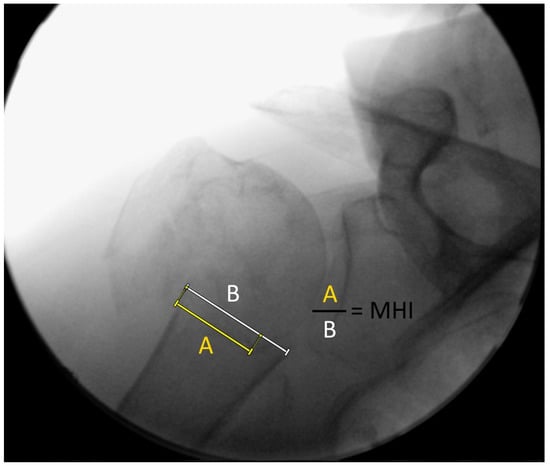

2.2. Fluoroscopic Analyses